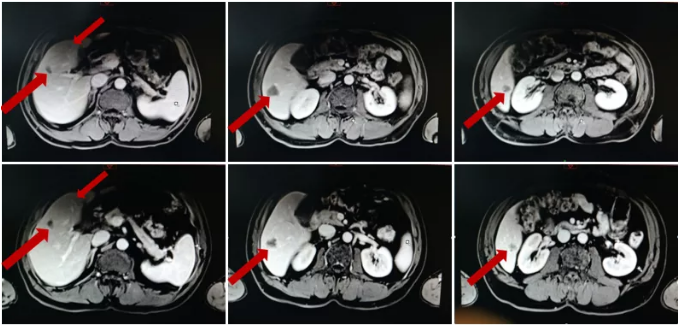

MRI复查结果:疗效评价PR(靶病灶缩小32%)。

化疗前后病灶变化情况

术后MRI复查:

病灶变化情况

MRI复查结果: